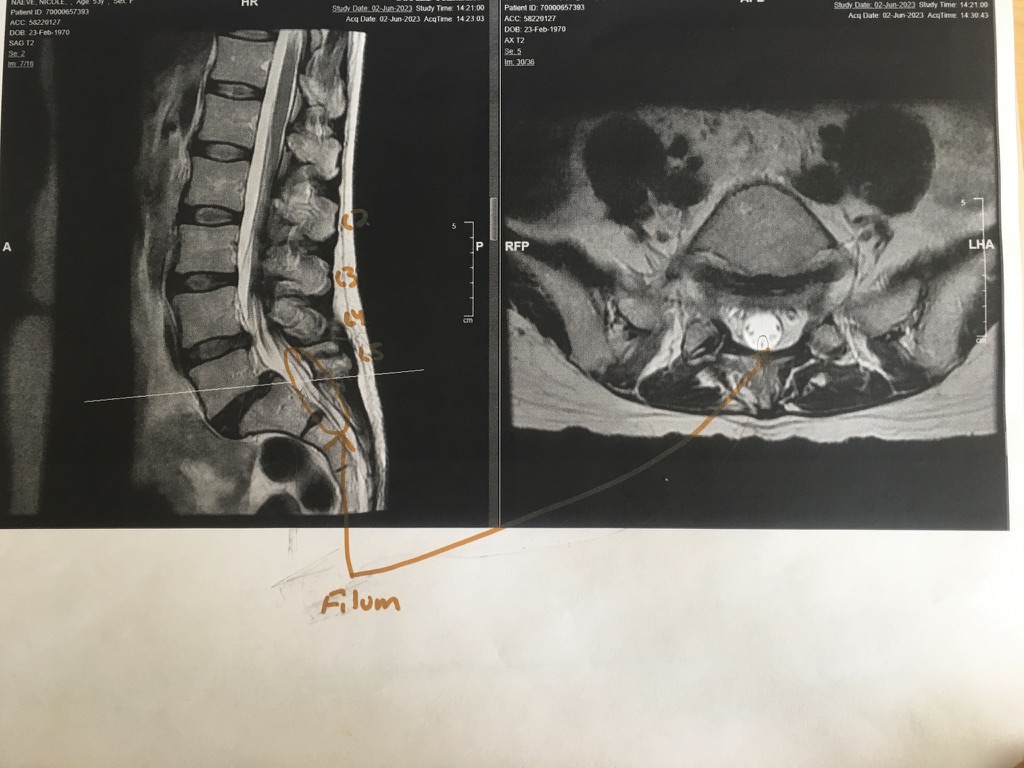

Here Dr. Klinge showed me where normal spinal cords should terminate at the bottom, and where mine ends. (Mine ends lower, because it’s tethered.)

Here the tethered filum is circled.

Close-up of the filum. This is what Dr. Klinge cut out and removed. The texture was tough, like grizzled meat, apparently – which is typical of tethered filums.

Another view of the tethered filum.